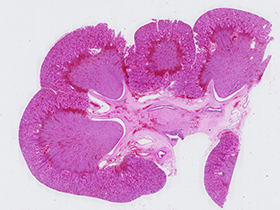

Riñón lobulado (tinción H&E)